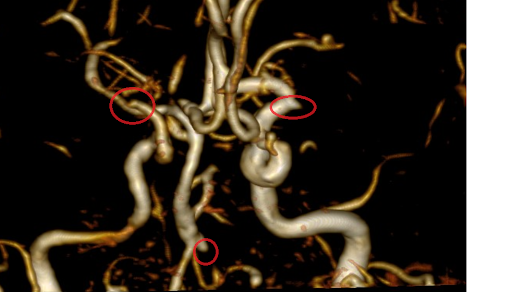

Bệnh nhân nam trẻ, 43 tuổi, hoàn toàn khỏe mạnh, đi khám sàng lọc đột quỵ tại BVĐK Phương Đông. Các chuyên gia tại khoa CĐHA đã phát hiện túi phình động mạch não kích thước ~ 7mm, nếu không được phát hiện và điều trị, túi phình này có thể vỡ và gây đột quỵ, để lại hậu quả vô cùng nặng nề không chỉ cho khách hàng mà còn khiến hạnh phúc một gia đình sụp đổ.

Bệnh nhân 66 tuổi đi sàng lọc đột quỵ tại bệnh viện đa khoa Phương Đông phát hiện ổ dị dạng mạch (AVM) giống như búi giun. Nếu không được phát hiện và điều trị, ổ dị dạng này có thể vỡ và gây hậu quả vô cùng nặng nề.